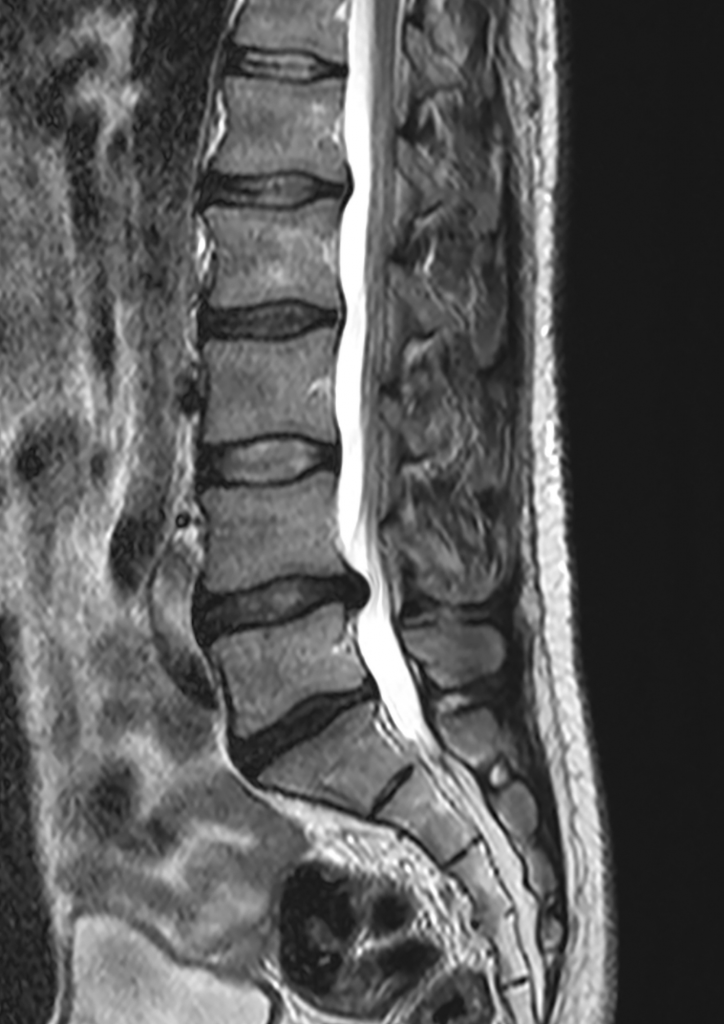

Przepuklina kręgosłupa

Siedzący tryb życia, a także brak odpowiedniej ilości aktywności fizycznej w sposób bezpośredni wpływają na powstawanie problemów z kręgosłupem u coraz młodszych osób. Przepukliny kręgosłupa są coraz częściej diagnozowane u osób zmagających się z dolegliwościami bólowymi kręgosłupa.

Termin ten odnosi się do choroby krążka międzykręgowego. Krążek międzykręgowy, znajdujący się pomiędzy trzonami kręgów, pełni przede wszystkim funkcję amortyzującą wstrząsy oraz zapewnia ruchomość kręgosłupa. Składa się on z wewnętrznie położonego jądra miażdżystego oraz zewnętrznie położonego pierścienia włóknistego.

Pod wpływem wieloletnich obciążeń, siedzącego trybu życia, braku aktywności fizycznej oraz codziennych złych nawyków w funkcjonowaniu, krążek międzykręgowy może tracić swoje właściwości, a pełnione przez niego funkcje zostają zaburzone.

Z biegiem czasu włókna pierścienia włóknistego ulegają osłabieniu, a jądro miażdżyste uwypukla się – jest to tzw. wypuklina kręgosłupa.

Gdy dochodzi do całkowitego rozerwania włókien pierścienia włóknistego, a jądro miażdżyste wydostaje się poza jego obręb, często uciskając korzenie nerwów rdzeniowych, powstaje tzw. przepuklina kręgosłupa.

Do wspomnianych powyżej zmian w obrębie krążka międzykręgowego może dojść w każdym odcinku kręgosłupa. Najczęściej jednak zmiany te dotyczą odcinka lędźwiowego oraz szyjnego. Objawy są bardzo zróżnicowane i specyficzne dla danego odcinka kręgosłupa.